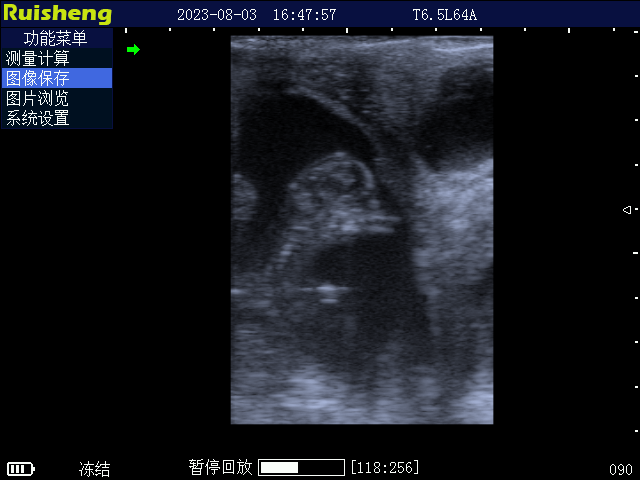

C8 牛用全数字B超诊断仪

• 【 畜牧业超声 】 C8 牛用全数字B超诊断仪 适用对象:[ 牛、羊、猪、马、骆驼、猫、狗 ]

产品介绍

8. 支持电子凸阵探头、直肠探头、微凸探头、高频线阵探头、羊用带把手专用探头、背膘探头